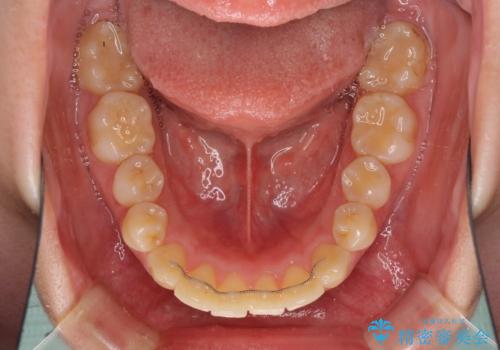

- クリアブラケット

- 上下前歯を部分矯正したところ出っ歯になってしまったとのことで来院された患者様です。

上下左右第一小臼歯4本を抜歯して、積極的に口元を引っ込めるよう、ワイヤー装置にて矯正治療を行うこととしました。

治療後には口が閉じやすくなり、患者様には大変満足していただきました。